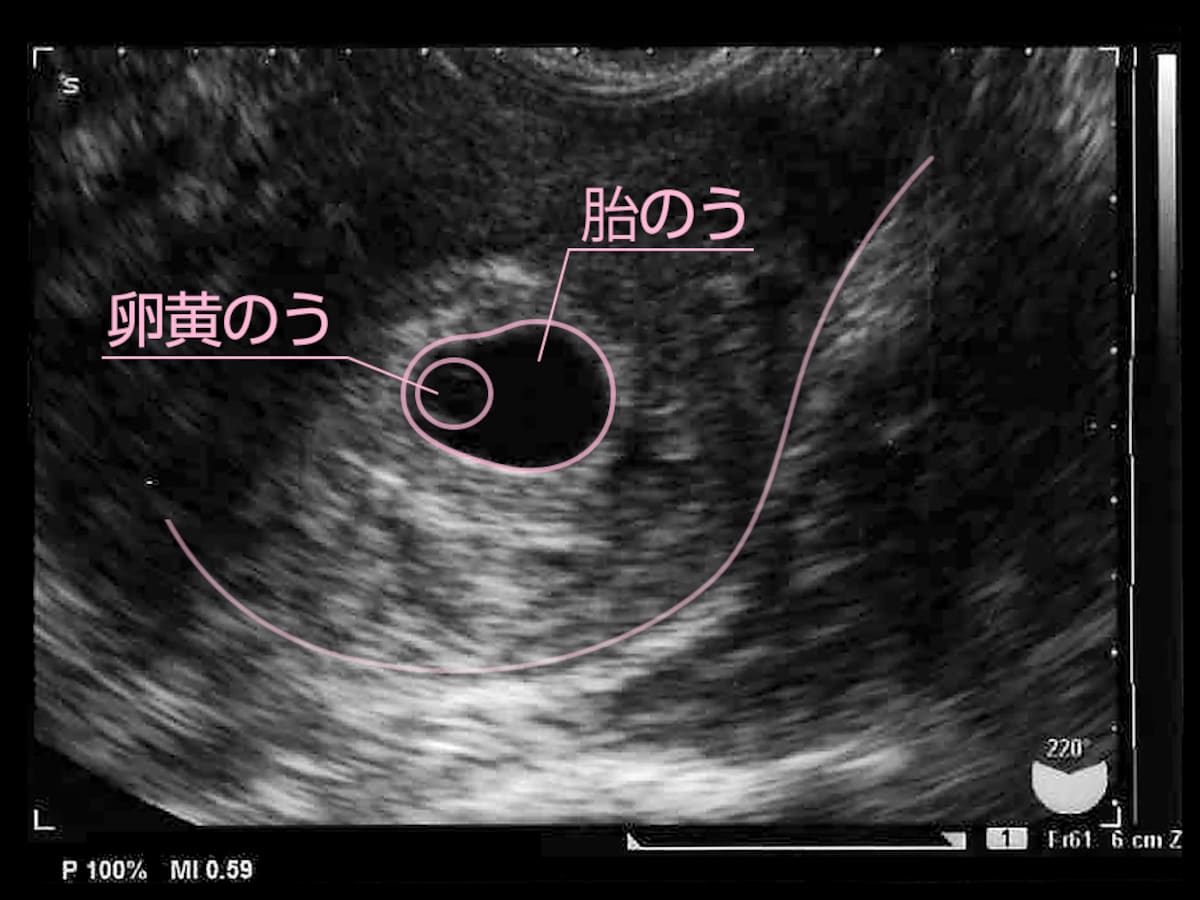

5 産科一般超音波検査 初期編 正常所見4 7週 日本産婦人科医会

5 産科一般超音波検査 初期編 正常所見4 7週 日本産婦人科医会

5 産科一般超音波検査 初期編 正常所見4 7週 日本産婦人科医会

5 産科一般超音波検査 初期編 正常所見4 7週 日本産婦人科医会

超音波写真館 妊娠初期4 7週 超音波教室 ママニティ大百科